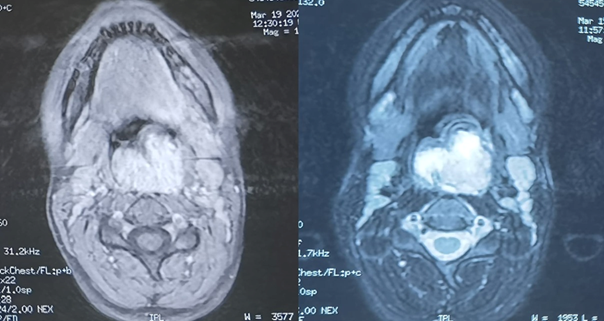

MRI was performed showing a pharyngeal process affecting the posterior

pharyngeal wall and compressing the oropharyngeal airway.

The mass appears well-defined, roughly oval in shape, with irregular contours.

It exhibits isosignal on T1 and heterogeneous hypersignal on T2 imaging. Post

Gadolinium injection, it shows intense and heterogeneous enhancement. Its was

measuring approximately 40x30.5 mm, extending to 48 mm. It displaces the

epiglottis and extends to the supraglottic level, filling the left piriform

sinus completely and the right piriform sinus partially. It comes into intimate

contact, with loss of separation line in places, with the left palatine tonsil.

Posteriorly, It comes into contact with the vertebral bodies of C2-C3 and C4

without osseous lysis, as well as the intervertebral discs of C2-C3 and C3-C4. (Figure 2).

Figure

2: Facial MRI performed showing a

pharyngeal process affecting the posterior pharyngeal wall